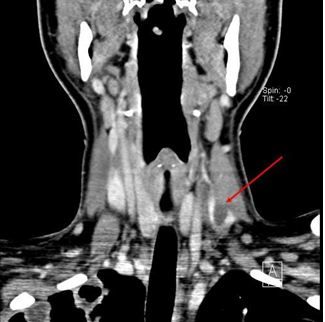

Fig 3. CT neck, coronal view shows thrombus in left internal jugular vein.

Later, a CT scan of the neck was performed. Results showed mild nonspecific thickening of the left tonsillar pillar and a thrombus in left internal jugular vein (Figures 2, 3, and 4, click to enlarge).